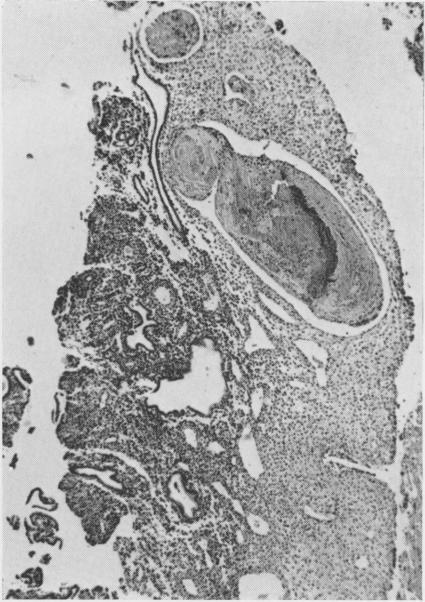

19-nor steroids in high and medium dosage in continuous or cyclic combined regimens with oestrogen produce an endometrium characterized by hyperinvoluted glands, a prominent predecidual reaction, suppressed arterioles, and dilated venules. When daily dosage is decreased to 2.0 mg. or less, the endometrium is composed of hyperinvoluted glands in an inert stroma; predecidual reactions are weak and infrequent; venules are rarely dilated, but spiral arterioles are suppressed.17-alpha-Acetoxyprogesterone derivatives in high and medium dosage given in a cyclic combined regimen with oestrogen produce similar but less intense effects to the 19-nor steroids. When given in cyclic sequential regimen, they produce an early secretory endometrium closely resembling normal patterns, chronologically retarded by about five days; in some instances a regressing, undatable secretory pattern is found, but predecidual response is minimal, and dilated venules are not seen.19-nor steroids in medium dosage given for 20 days without added oestrogen produce a late secretory endometrium with unpredictable variation from patient to patient and even from site to site within the same endometrium. Inhibition of the development of spiral arterioles is a common denominator in all progestagenoestrogen regimens. Modification of this element within the target tissue may be decisive for the morphogenesis of later vascular and stromal changes. Using synthetic progestagen-oestrogen regimens, endometrial gland secretion appears only after progestagen, whether given ab initio concomitantly with oestrogen or begun after a phase of oestrogen priming. Secretory vacuoles become evident about four to five days after progestagen is administered. The role of progestagen in secretion is interpreted as an indirect effect whereas its role in the development of decidual-like changes is construed as direct.

19-去甲甾体类药物以高剂量和中等剂量与雌激素连续或周期性联合使用时,会使子宫内膜呈现出以下特征:腺体过度退化、明显的蜕膜前反应、小动脉受抑制以及小静脉扩张。当每日剂量降至2.0毫克或更低时,子宫内膜由处于惰性基质中的过度退化腺体组成;蜕膜前反应微弱且不常见;小静脉很少扩张,但螺旋小动脉受到抑制。17-α-乙酰氧基孕酮衍生物以高剂量和中等剂量与雌激素周期性联合使用时,会产生与19-去甲甾体类药物相似但程度较轻的效果。当以周期性序贯方案给药时,它们会产生一种早期分泌期子宫内膜,与正常模式非常相似,但时间上延迟约五天;在某些情况下,会发现一种退行性、无法确定日期的分泌模式,但蜕膜前反应极小,且未见小静脉扩张。19-去甲甾体类药物以中等剂量连续20天给药且不添加雌激素时,会产生晚期分泌期子宫内膜,不同患者之间甚至同一子宫内膜内不同部位之间都存在不可预测的差异。抑制螺旋小动脉的发育是所有孕激素-雌激素方案的共同特征。在靶组织内对这一要素的改变可能对后期血管和基质变化的形态发生起决定性作用。使用合成孕激素-雌激素方案时,无论孕激素是一开始就与雌激素同时给药,还是在雌激素预处理阶段之后开始给药,子宫内膜腺体分泌都只会在给予孕激素之后出现。在给予孕激素约四到五天后,分泌空泡变得明显。孕激素在分泌中的作用被解释为间接作用,而其在蜕膜样变化发展中的作用则被认为是直接作用。